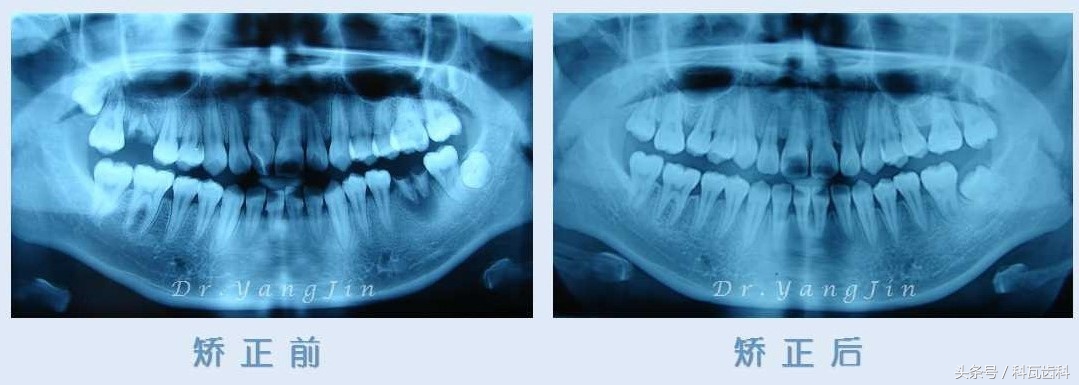

通过一系列检查包括X光片及牙模,牙齿实际现状为:上下牙列轻度拥挤不齐,右上中切牙扭转外翻,前牙对刃咬合,上颌中线右偏1mm,右侧上颌第一磨牙残根,左侧下颌第一磨牙残根、慢性根尖炎。

首先拔除右侧上颌第一磨牙残根,左侧下颌第一磨牙残根;经过固定矫治27个月,上下牙列排列整齐,覆合覆盖正常,

然后,类似“移花接木”的概念,牵引右侧上颌第二磨牙至右侧第一磨牙处,及左侧下颌第二磨牙至左下第一磨牙处,等待第三磨牙(智齿)自然萌出至第二磨牙位置。

整个正畸疗程顺利完成,小静保存了全口28颗牙齿,咬合关系良好,免去了种植修复两颗第一磨牙!这组是矫正X光片前后对比图,效果非常明显直观!